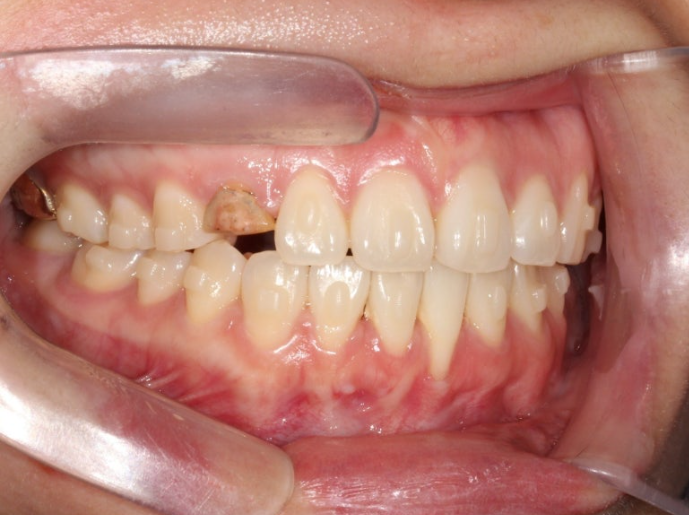

오래 전 했던 교정으로 어금니 교합은 나쁘지 않은 상태입니다.

인비절라인 라이트로 앞니 배열과 뿌리를 뼛속으로 깊이 넣어주는 치료를 권유드렸습니다.

위 앞니가 한쪽으로 기울어져 있는데다가 한쪽 송곳니가 안보이니 앞니 교합평면 기울어짐이 심해보입니다. 캔팅이라고 하죠.

이런 부분까지 개선되도록 치료계획에 반영됩니다.